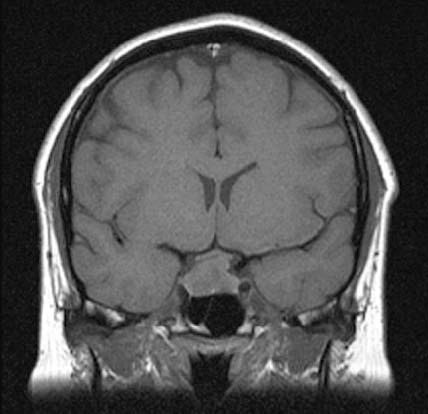

A 32-year-old woman presented to the outpatient clinic with a 1-year history of amenorrhoea that began after stopping her oral contraceptive pill. She had previously had two successful pregnancies and was otherwise well. Examination was normal and no visual field defect was present on testing to confrontation.

Investigations:

-serum sodium138 mmol/L (137–144) serum potassium3.8 mmol/L (3.5–4.9)

-plasma follicle-stimulating hormone2.0 U/L (2.5–10.0) plasma luteinising hormone2.0 U/L (2.5–10.0)

-serum prolactin1050 mU/L (<360) MR scan of pituitarysee image

What is the most appropriate treatment?

1. bromocriptine

2. cabergoline

3. octreotide

4. pituitary surgery

5. stereotactic pituitary radiosurgery

Answer(s): D